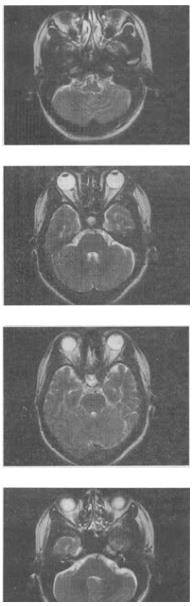

女,41岁,阵发性头痛伴恶心,呕吐20余天,MRI影像如图,最可能的诊断是()。

A、双侧筛窦息肉

B、双侧筛窦炎

C、双侧筛窦未见明显异常

D、双侧筛窦真菌感染

E、双侧筛窦过敏性炎症

B